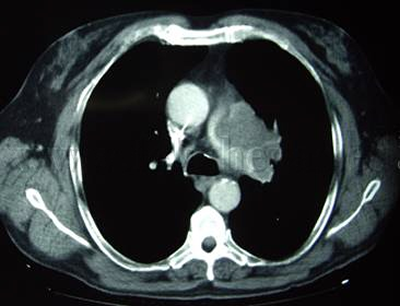

Cáncer de pulmón